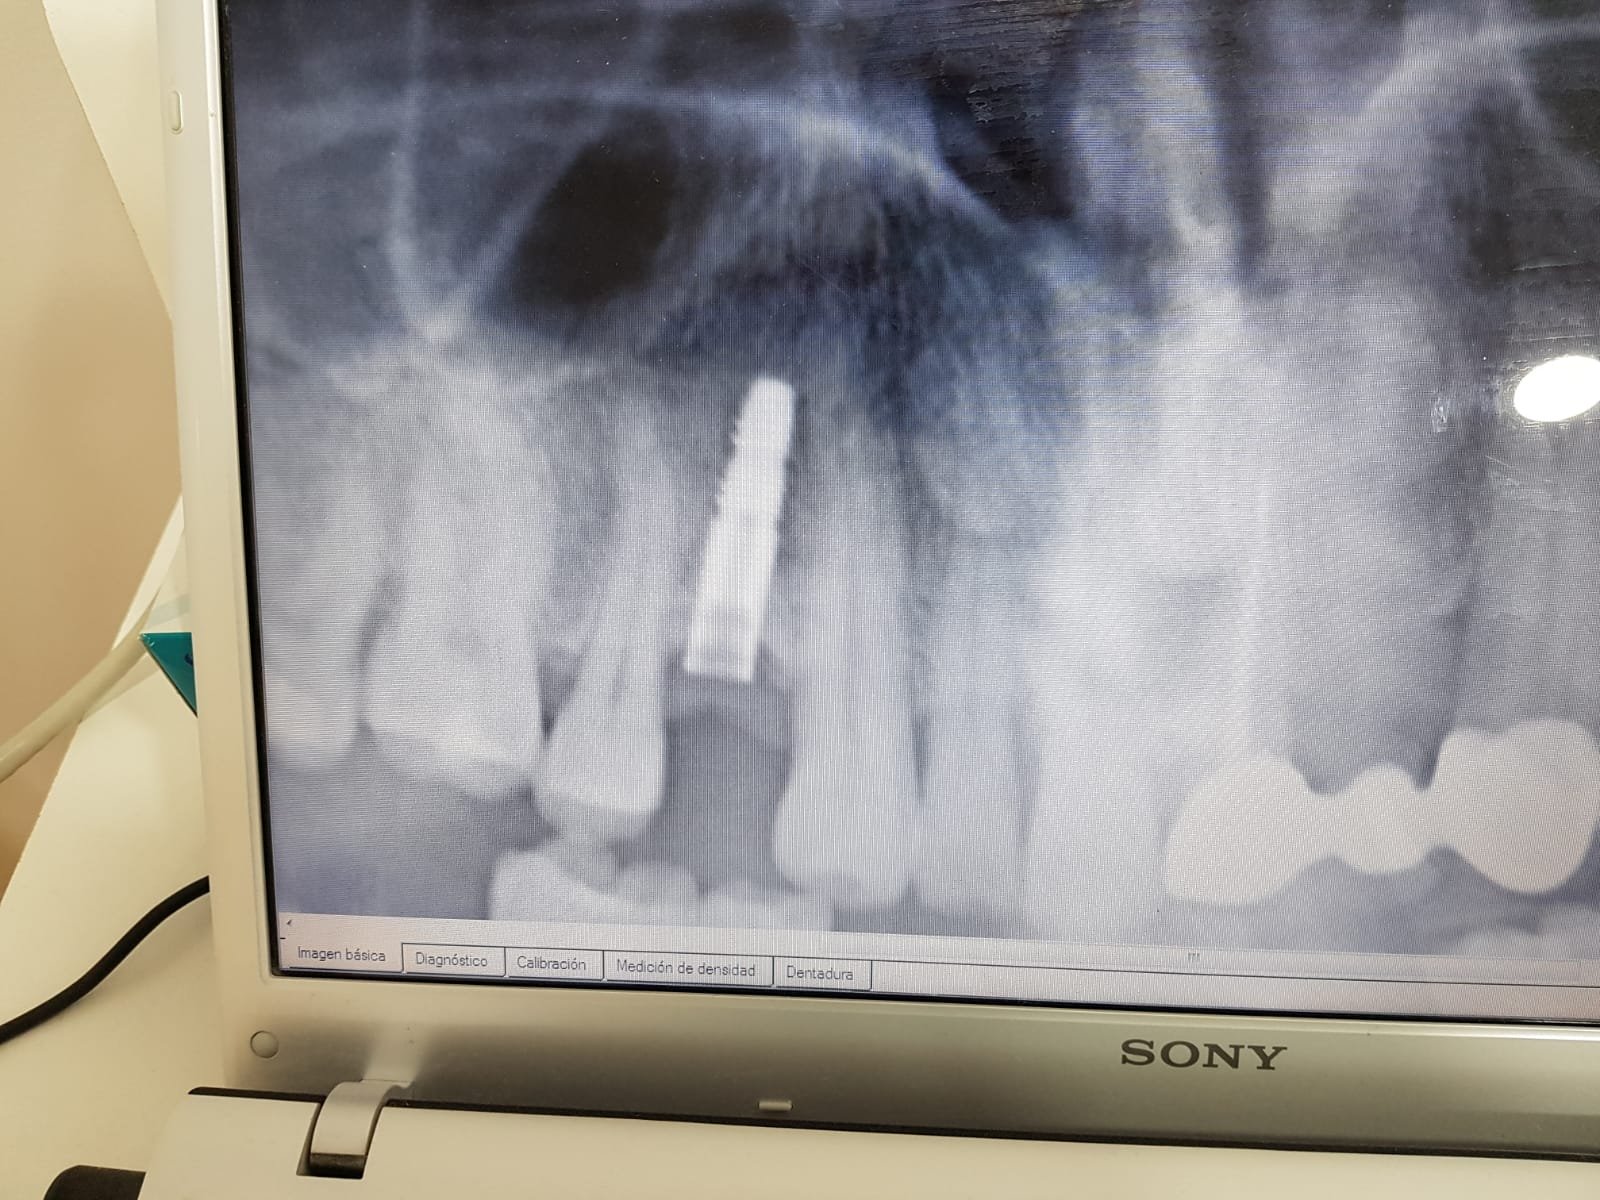

Buenos días!Me podríais ayudar con la marca de este implante?! Muuuchas gracias!!

Buenos días, colegas. Agradecería, por favor identificar este tipo de implantes, según el paciente llevan en boca unos 12 años. Cordiales saludos.

Buenos días. Ayer me vino una paciente Belga con la corona en la mano y el tornillo fracturado. Gracias por vuestra ayuda.